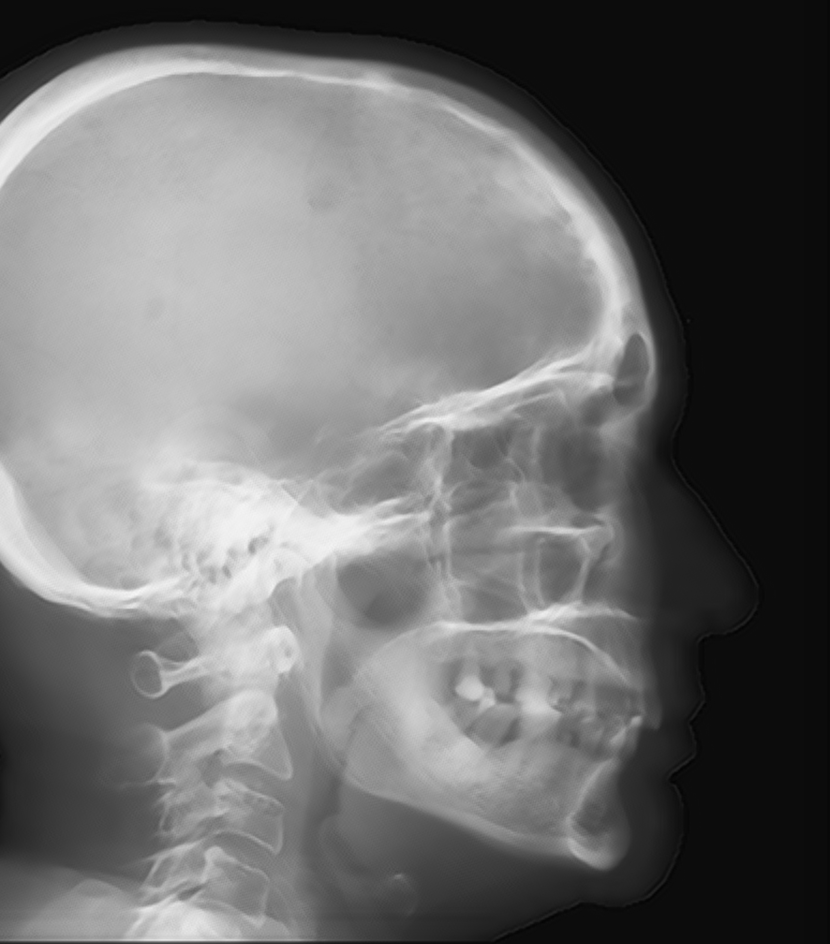

Refer to caption

Fig. 15: Accuracy comparison of different cephalometric landmark detection algorithms [16, 27, 1, 40, 7, 46] on ISBI Testset1 and Testset2.

To validate the efficacy of our proposed automatic landmark detection algorithm, it is compared with other state-of-the-art algorithms on the benchmark ISBI data (Testset1 and Testset2). The SDRs of different algorithms [16, 27, 1, 40, 7, 46] in different precision ranges for Testset1 and Testset2 are displayed in Fig. 15(a) and (b), respectively. Our proposed method achieves the 2 mm-SDRs of 86.7% and 73.7% on the ISBI Testset1 and Testset2, respectively, which is comparable to the best accuracy methods [7, 46]. However, our method is more efficient than [7] and has a simpler architecture than [46].